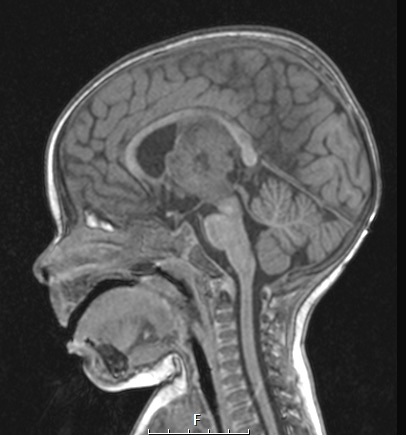

A T1-weighted image of the mass shows iso/hypointensity in comparison to the adjacent brain and brainstem.